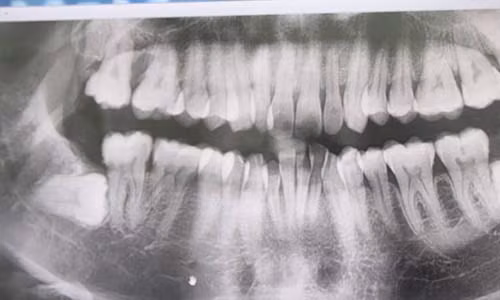

| Phụ nữ trong độ tuổi sinh đẻ cần nhổ răng khôn mọc lệch trước khi có ý định mang bầu. Trong ảnh, răng khôn mọc ngang, húc vào răng số 7. |